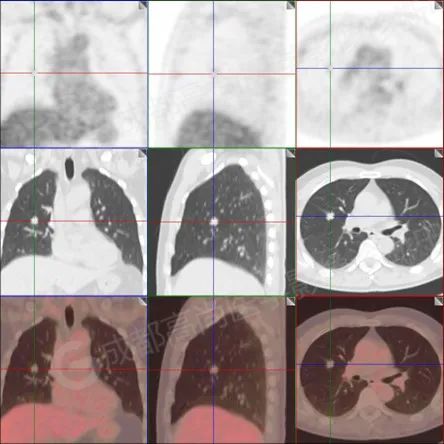

PET/CT 显影图像如下:

【PET/CT 融合图】

PET/CT 检查示:

右肺上叶前段及右肺中叶外侧段分叶状软组织结节,该病变骑跨水平裂胸膜,大小约 1.5 cm×1.3 cm×1.6 cm(上下径),边界清晰,其内密度欠均匀,CT 值约 18 Hu,FDG 摄取未见明显增高。

PET/CT 诊断:1. 右肺上叶前段及右肺中叶外侧段见一分叶状软组织结节影(约 1.5 cm×1.3 cm×1.6 cm),该病变骑跨水平裂胸膜,FDG 摄取未见明显增高,考虑为良性肿瘤,请结合病理协诊。